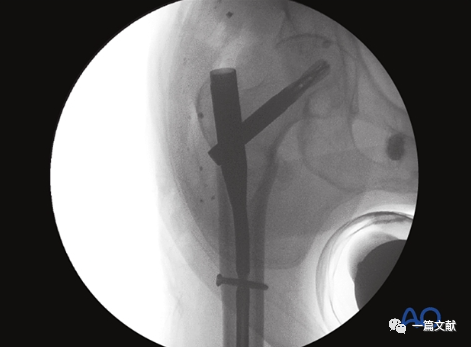

下图左侧正位片与右侧的轴位片,显示了内固定的良好位置(位于头颈中心与髓腔中心)。需要注意的是这些标准的术中透视图像,只有在良好骨折复位的基础上才能获得。

只有如下图右侧的轴位片图像才能判断内固定在头颈骨块中的位置(左侧为侧位片)

同一患者的侧位像与轴位像的内固定透视图像如下图: